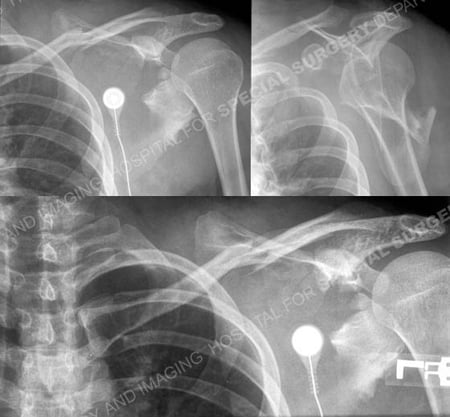

A 25-year-old male lost control while riding a moped and fell landing on his outstretched left upper extremity. He was taken to a local hospital and radiographs revealed a complex comminuted left-sided scapula fracture with extension into the glenoid and an associated mid-shaft clavicle fracture. Open Reduction and Internal Fixation (ORIF) for the clavicle fracture was performed at the outside hospital using a plate placed on the superior aspect of the clavicle.

Anteroposterior and lateral radiographs illustrating a complex comminuted left-sided scapula fracture with extension into the glenoid and an associated mid-shaft clavicle fracture.

3D reformatted CT scan images further delineate the fracture pattern.